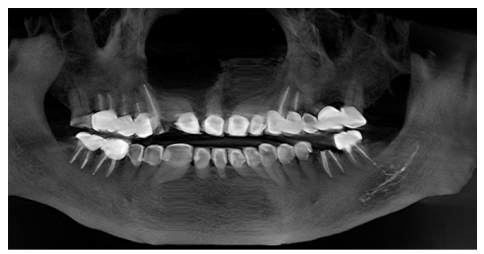

初诊时带来的5年前曲面体层片,如下图。

可见37冠部修复,根管内有高密度充填物影像,远中根管充填物沿伸至根尖周并进入左下颌管内,下颌管内有条状高密度影(近中至36远中根下颌管处,远中至下颌升支1/3处);初诊锥形束CT(CBCT)显示37根管内见高密度充填物影像,根尖周未见密度减低影,疑似大量充填糊剂沿37远中根进入下颌管内,并包绕于管壁。较5年前曲面体层片无明显变化。